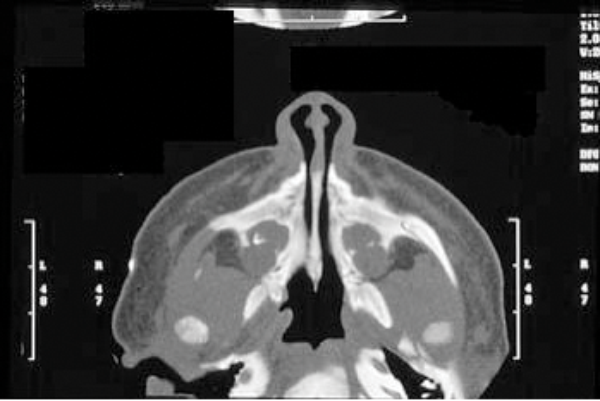

Management of CNPAS is dependent upon the individual infant and certain key clinical factors including growth, feeding and sleeping patterns and the presence or absence of cyanotic events. Initial management includes establishing the diagnosis and assessing the severity of symptoms. A craniofacial computed tomography (CT) scan is the investigation of choice (Figure 1) and a pyriform aperture width (PAW) of <11mm is diagnostic of pyriform aperture stenosis. As a rule children with a PAW of less than or equal to 7mm usually require surgery whereas those with a PAW of >7mm may be managed conservatively.

Figure 1: A craniofacial CT scan demonstrating CNPAS.